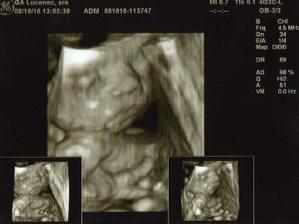

Nase 3D sono